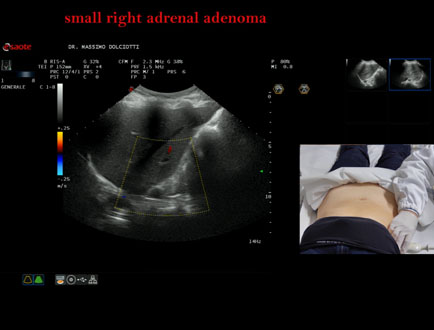

Età Paziente: F 69 anni

Motivazione dell'esame: follow up per piccolo adenoma surrenalico.

Commento all'esame: le immagini ed il video documentano in sede surrenalica destra, formazione ipoecogena, a margini definiti, rotondeggiante, delle dimensioni di 15,8 x 14,8 mm, da ricondurre ad adenoma surrenalico.

Conclusioni: piccolo adenoma surrenalico destro (small right adrenal adenoma).

Presentazione: Dr. Massimo Dolciotti - Ancona

Elaborazione digitale: Andrea Dini - Ancona